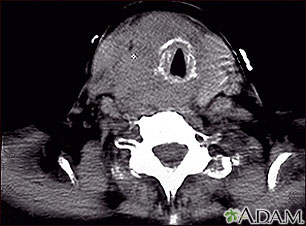

This CT scan shows a thyroid cancer tumor in the throat, encircling, narrowing, and displacing the windpipe (trachea).